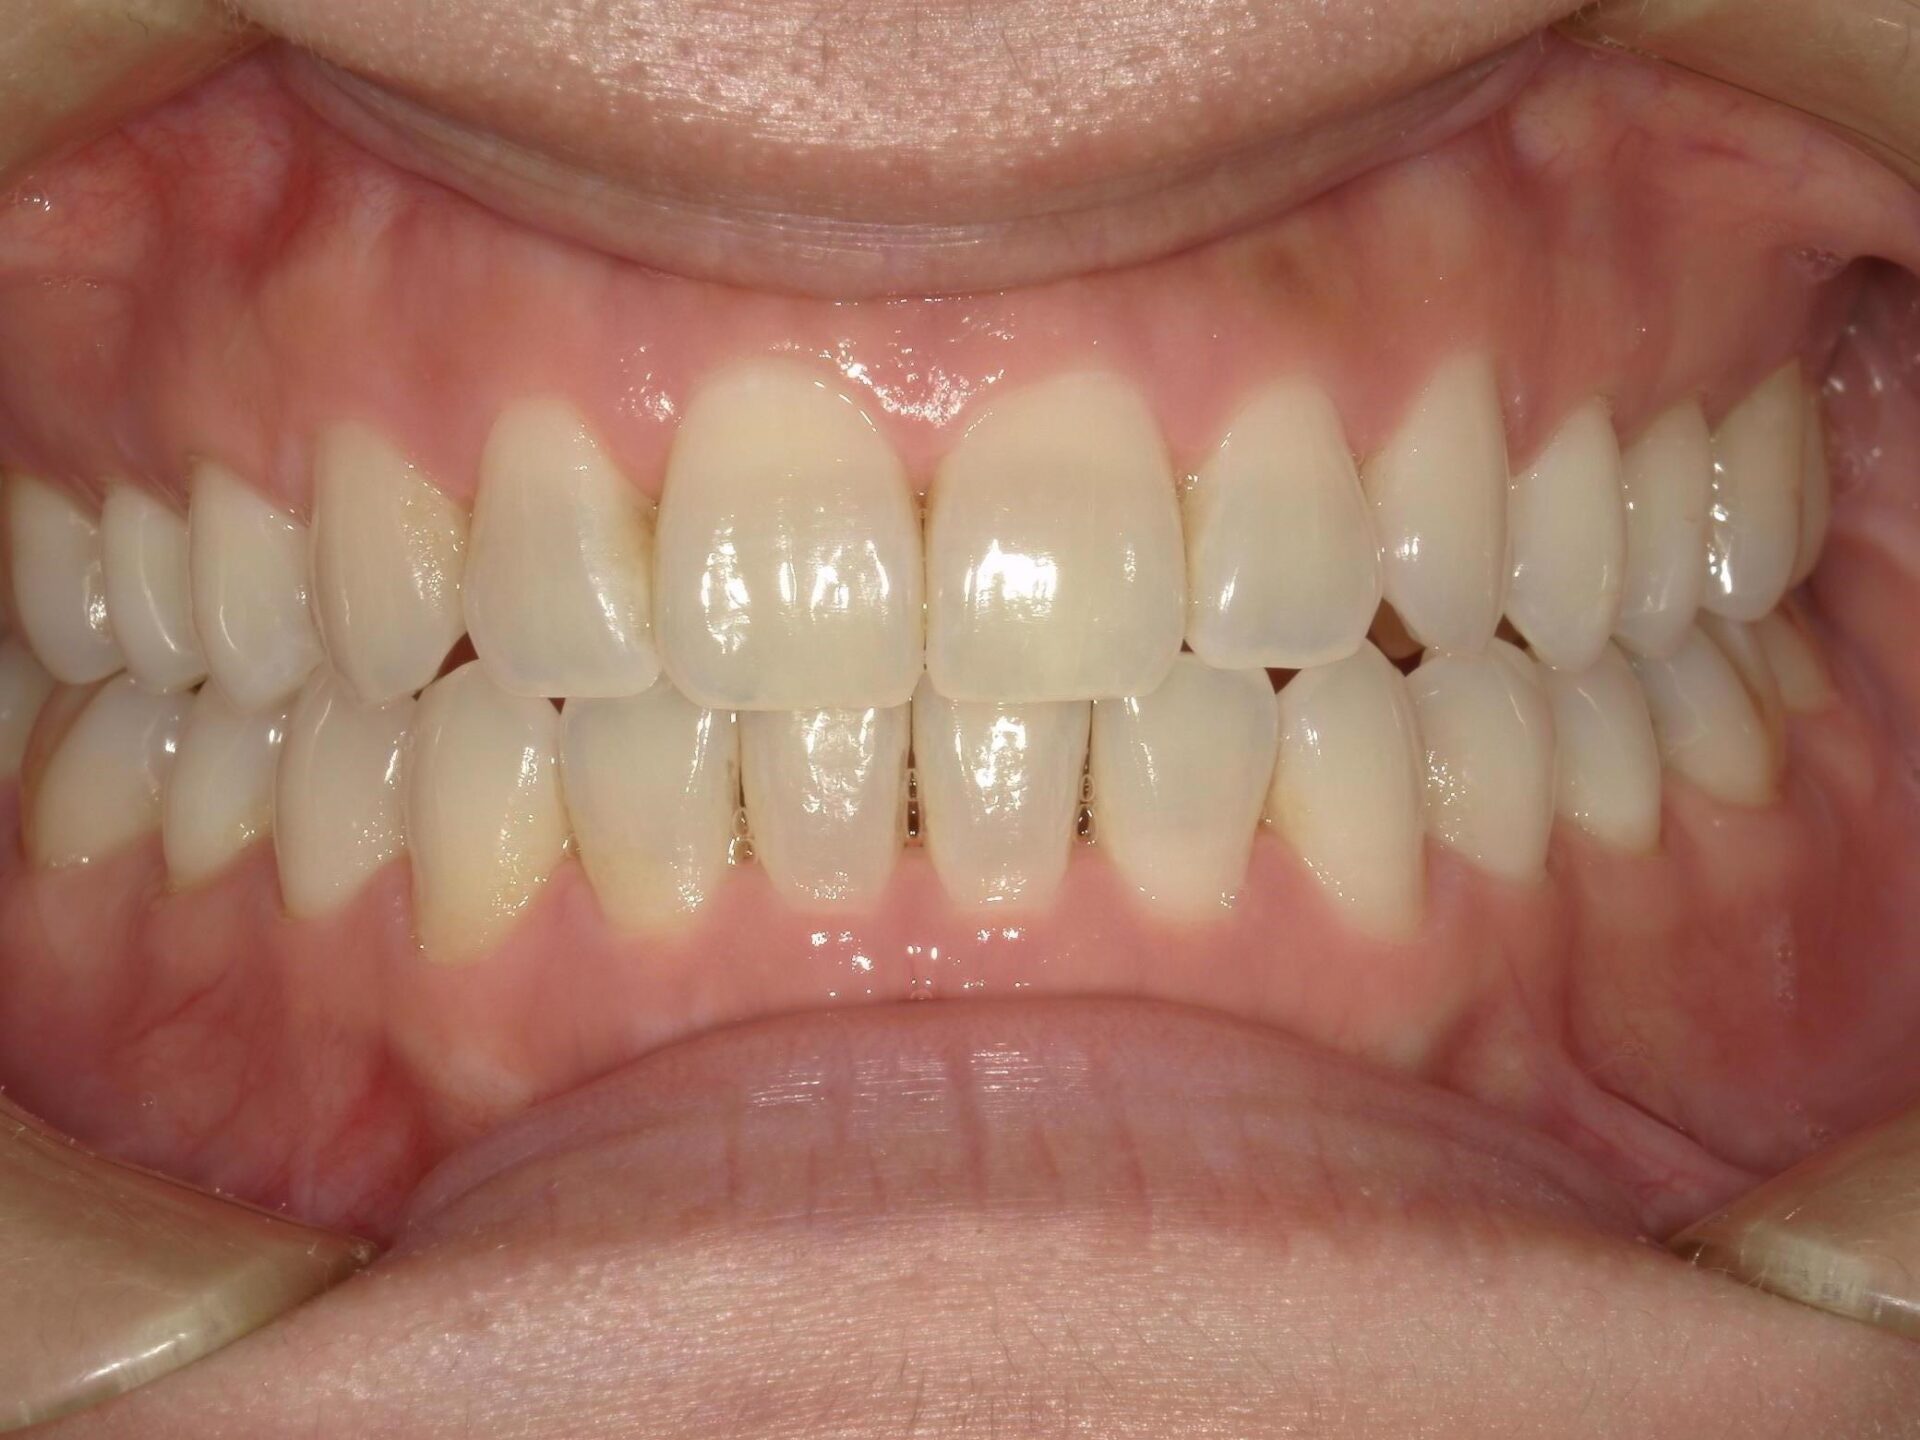

20代、女性、ワイヤー

| 施術内容 | 主訴:全体的に凸凹が気になる 詳細:ワイヤー矯正での歯並び改善 ずっと磨きにくく、臭いが気になっていましたが、 矯正後は磨きやすくなり、臭いも無くなって満足された症例です。 |

| 治療期間 | 16ヶ月(3/13現在 治療終了) |

| 費用 | ワイヤー矯正 60万円(税込660,000円) |